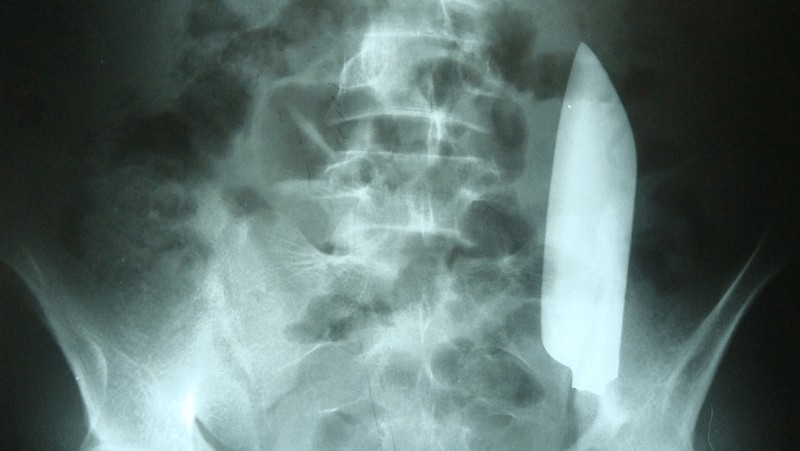

Hasil pemeriksaan CT Scan perut menunjukkan adanya bilah pisau sepanjang 15 cm di perut kiri bawah pasien. Kasus ini dipublikasikan di Jurnal Cureus pada 2023. (Foto: Jurnal Cureus).

Pasien kemudian dibawa ke ruang operasi dan pencitraan diulang di bawah fluoroskopi, yang mengungkapkan lokasi bilah pisau di dalam rongga perut. Laparotomi dilakukan, dan bilah pisau sepanjang 15 cm ditemukan di daerah iliaka kirinya. Untungnya, tidak ada cedera parah pada organ-organ di sekitarnya. (Foto: Jurnal Cureus).